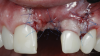

(3.) The crown was removed, and a partial thickness flap was reflected using a papilla-sparing incision design, which revealed that the implant was positioned too far facially and that its body was visible through a very thin layer of bone.

Figure 3

(4.) The crown was removed, and a partial thickness flap was reflected using a papilla-sparing incision design, which revealed that the implant was positioned too far facially and that its body was visible through a very thin layer of bone.

Figure 4